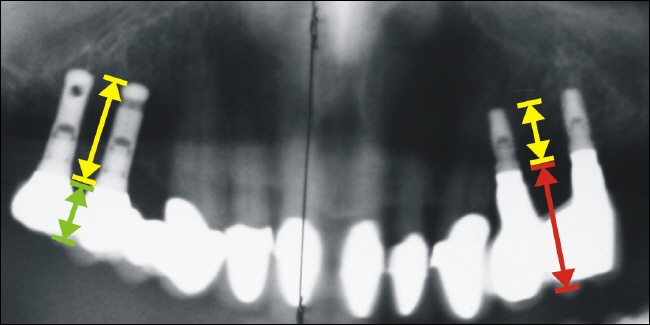

Statische Fehlversorgung

Die Pfeile verdeutlichen das statische Problem rechts auf dem Bild. Es besteht ein erhebliches Missverhältnis zwischen dem Kraftarm, symbolisiert durch den gelben Pfeil (entspricht der Implantatlänge), und dem Hebelarm, symbolisiert durch den roten Pfeil (entspricht der Kronenlänge).

Links im Röntgenbild zeigt sich dagegen ein günstiges Verhältnis von Kraftarm und Hebelarm.

Misserfolg durch Implantatverlust

Schon nach drei Jahren scheitert die Versorgung offensichtlich aufgrund der statischen Fehlkonstruktion. Das verbliebene Implantat ist nicht mehr nutzbar, lediglich eine Neuimplantation mit ausreichend langen Implantaten ist in diesem Fall sinnvoll.